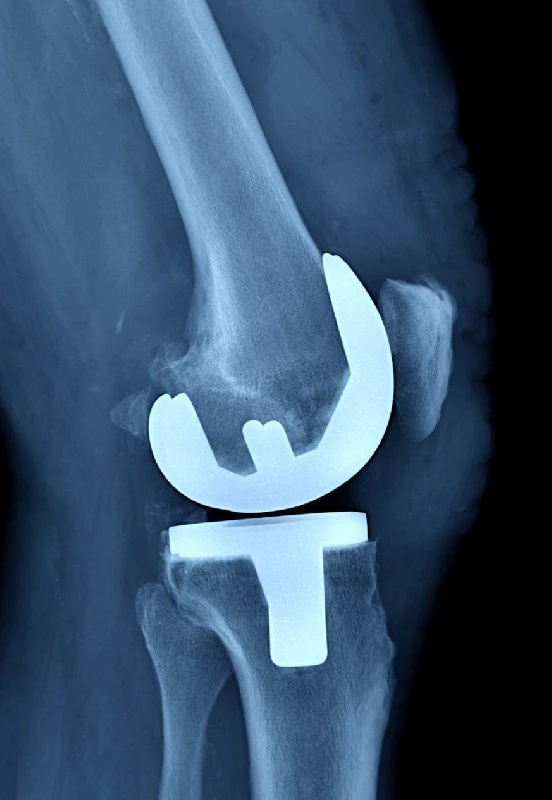

В Балахнинской ЦРБ начали выполнять операции по замене коленных суставов

В Балахнинской ЦРБ начали выполнять операции по замене коленных суставов.

Чаще всего артроз развивается из-за лишнего веса, перенесённых вирусных инфекций, сверхнагрузок, влияет и наследственность. После замены сустава исчезает боль, восстанавливается объём движений в суставе и способность опираться на ногу.

В больнице пациенты проводят не более недели, реабилитация после замены суставов занимает около 3-4 месяцев. Операции проводятся бесплатно, по полису ОМС, сообщает главный редактор ИА "Стационар-пресс" Алексей Никонов.

Фото: Алексей Никонов